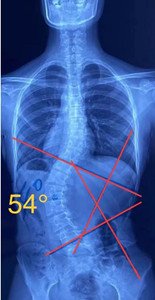

單向側(cè)彎

如果是單向側(cè)彎的患者,(腰彎或者胸彎),躺在床上,應(yīng)向患側(cè)處進行臥位,側(cè)臥在你彎弧的凹側(cè),讓它下墜打開。